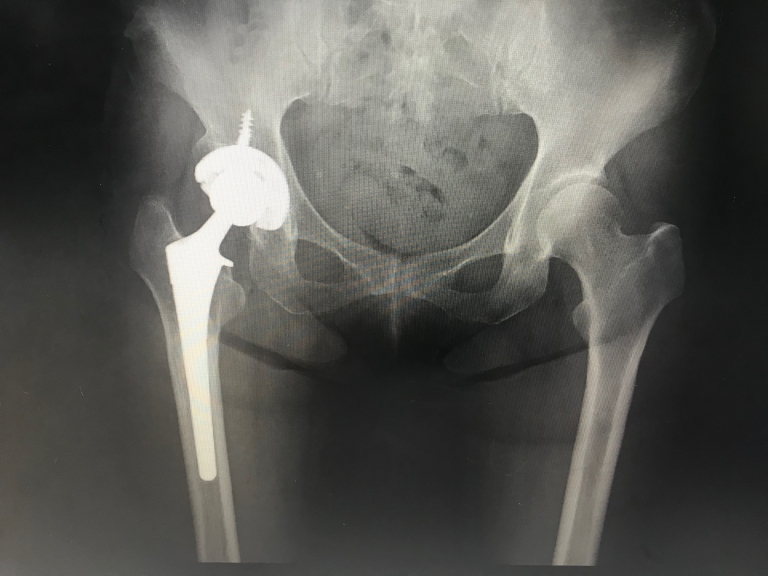

人工股関節(図4)はその器械と手術方法の発達により、幅広い年齢に行われるようになってきました。プロゴルファーをはじめ、プロスポーツ選手のなかにも人工股関節の手術を受けられて方もいらっしゃいますので、術後の生活の制限はかなり小さくなってきたといえます。

図4:人工関節

図4:人工関節のレントゲン画像